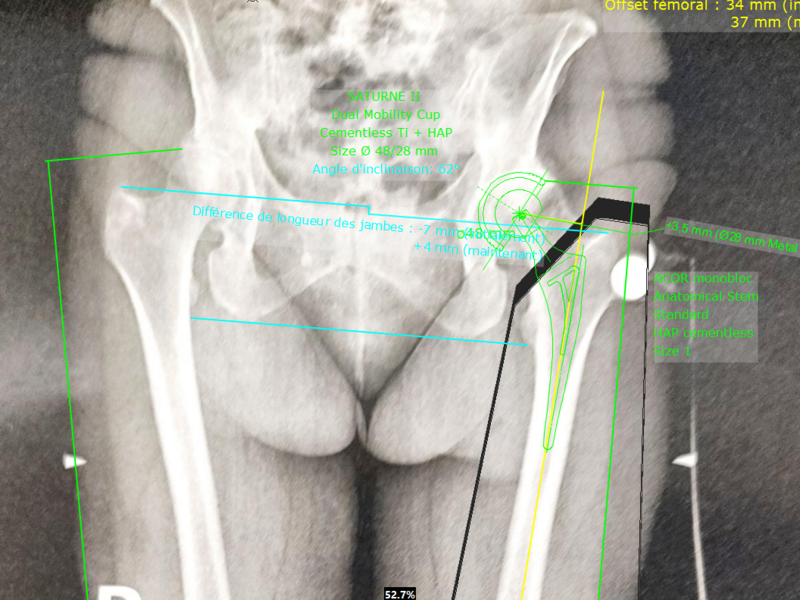

Album photo